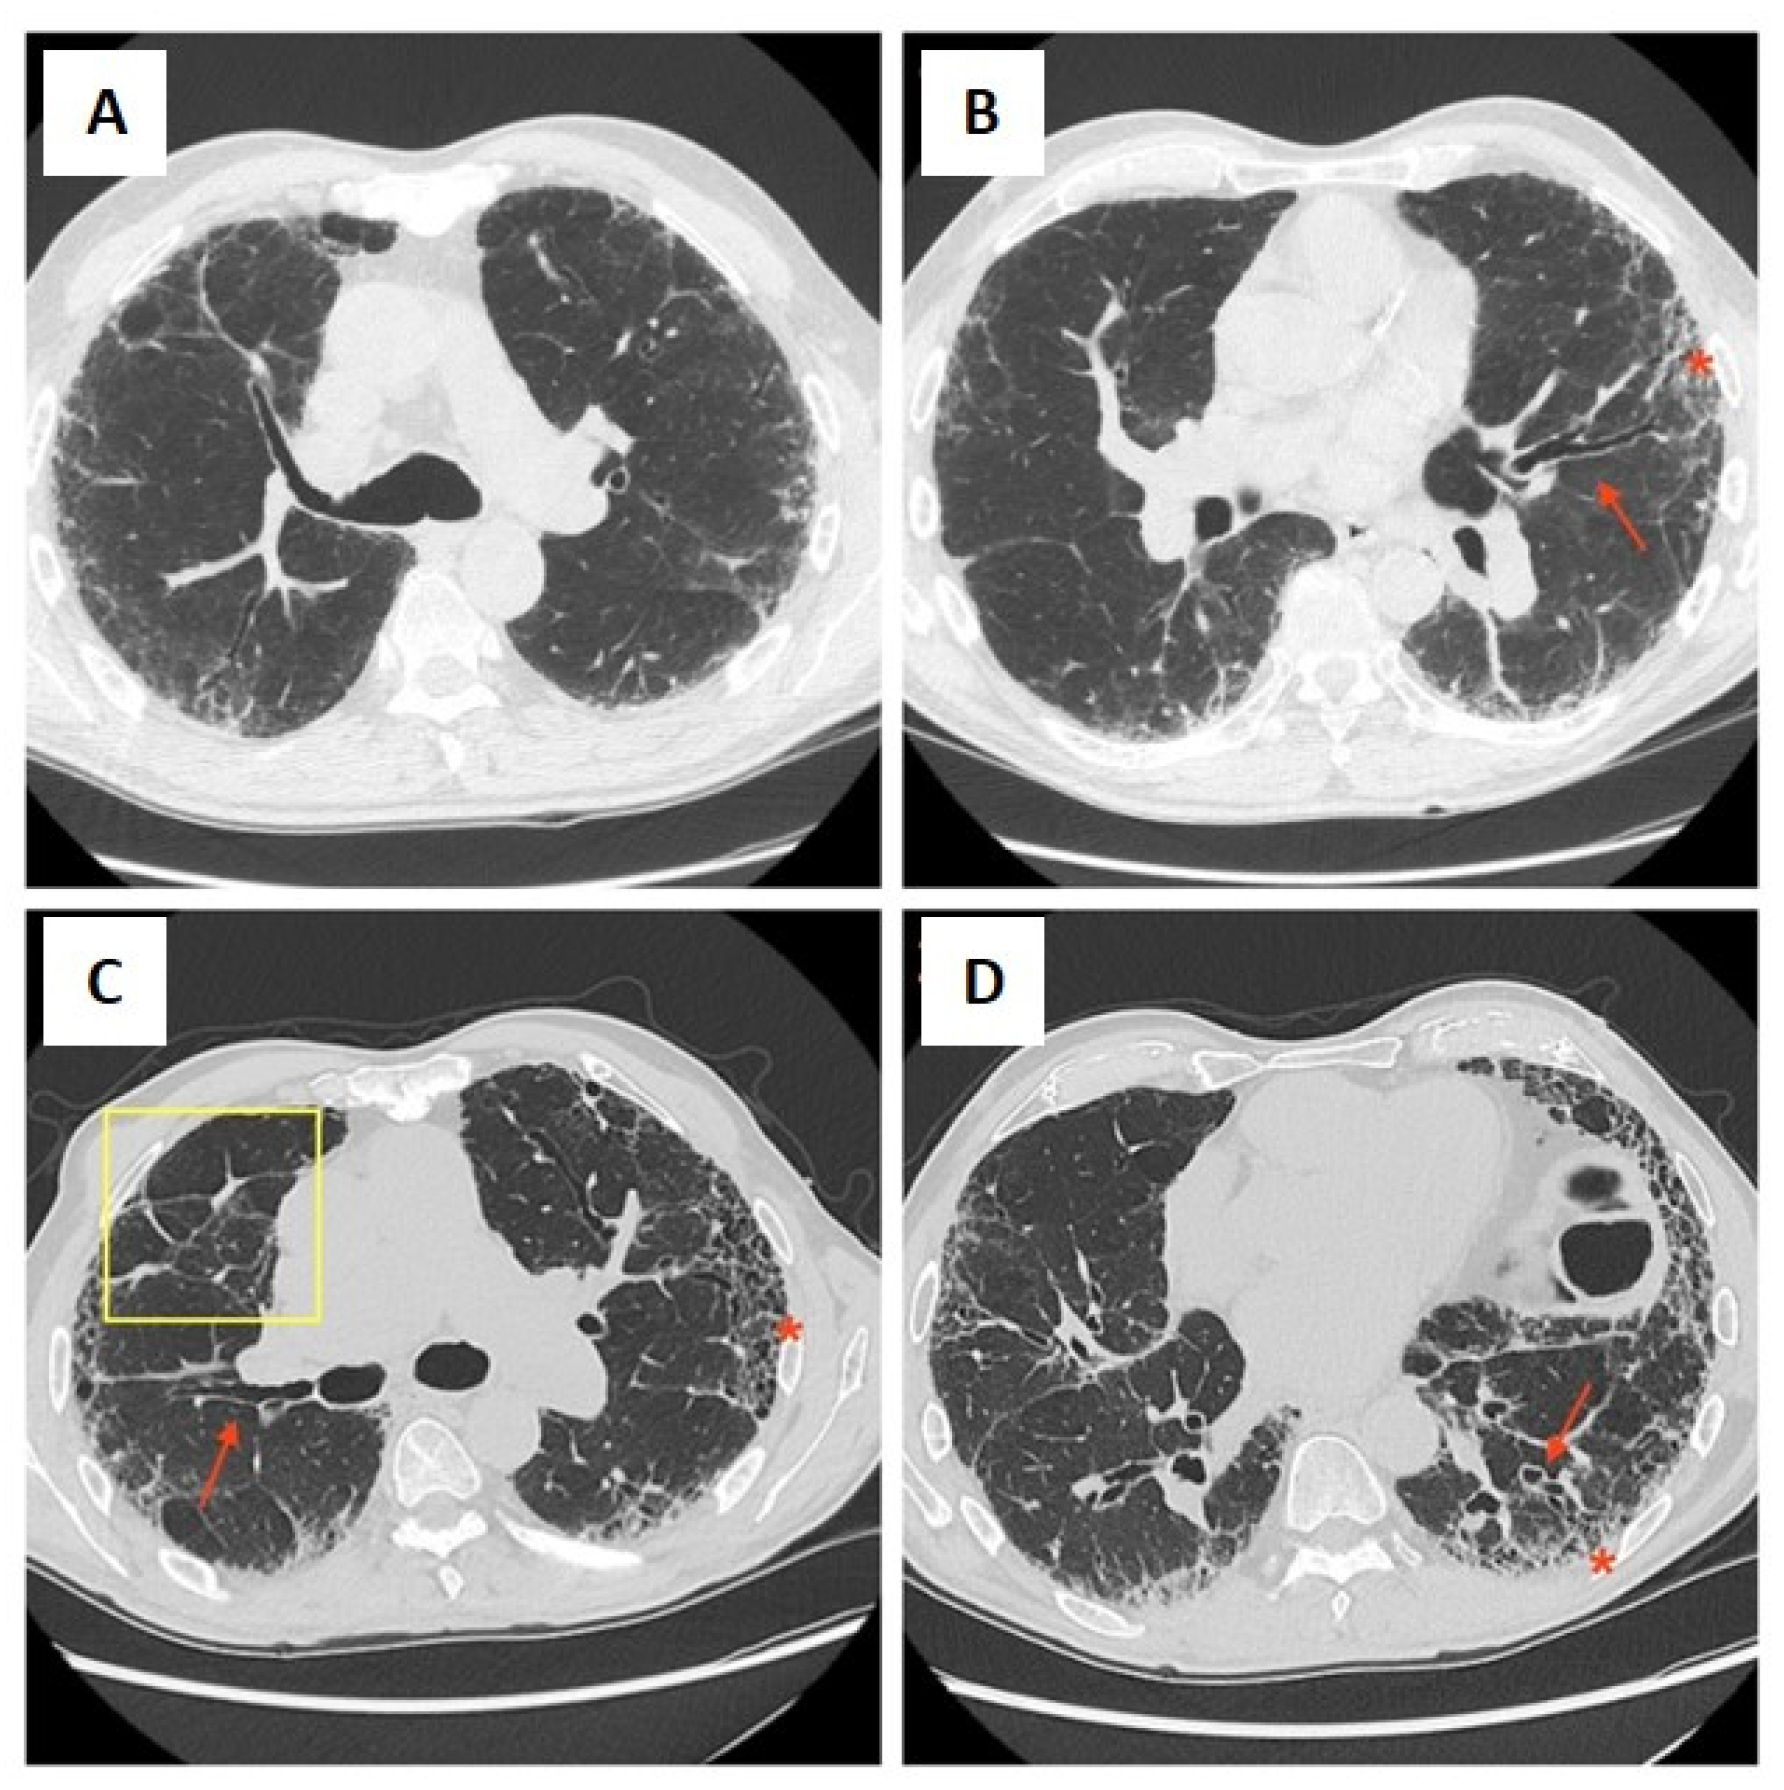

- Robledo, G.C.; Hernández, M.Y.J.; Lucas, S.A.G.; Delgado, F.R.C. Combined Pulmonary Fibrosis and Emphysema With Pulmonary Hypertension: Cases Report. Curr. Probl. Cardiol. 2022, 47, 100856. [Google Scholar] [CrossRef] [PubMed]